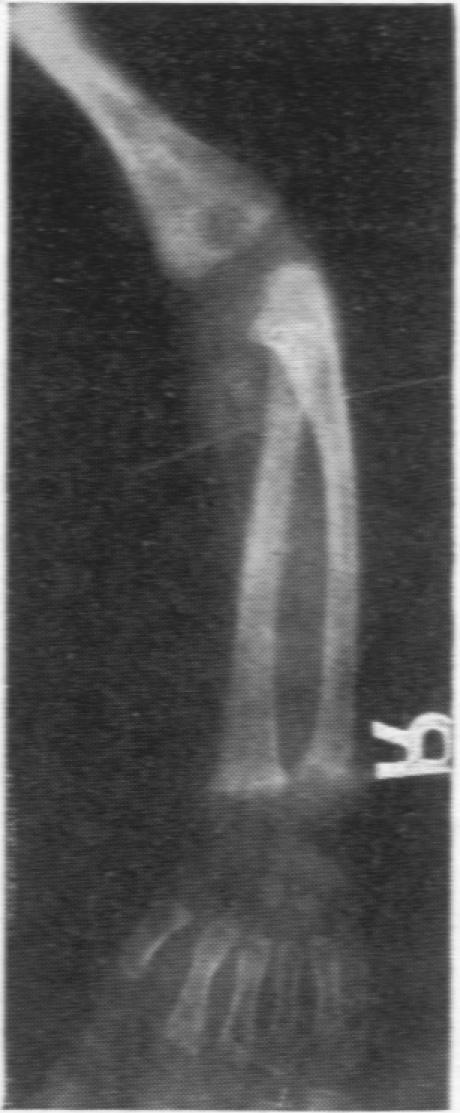

BABER M D

Arch Dis Child. 1956 Oct;31(159):335-9. doi: 10.1136/adc.31.159.335.